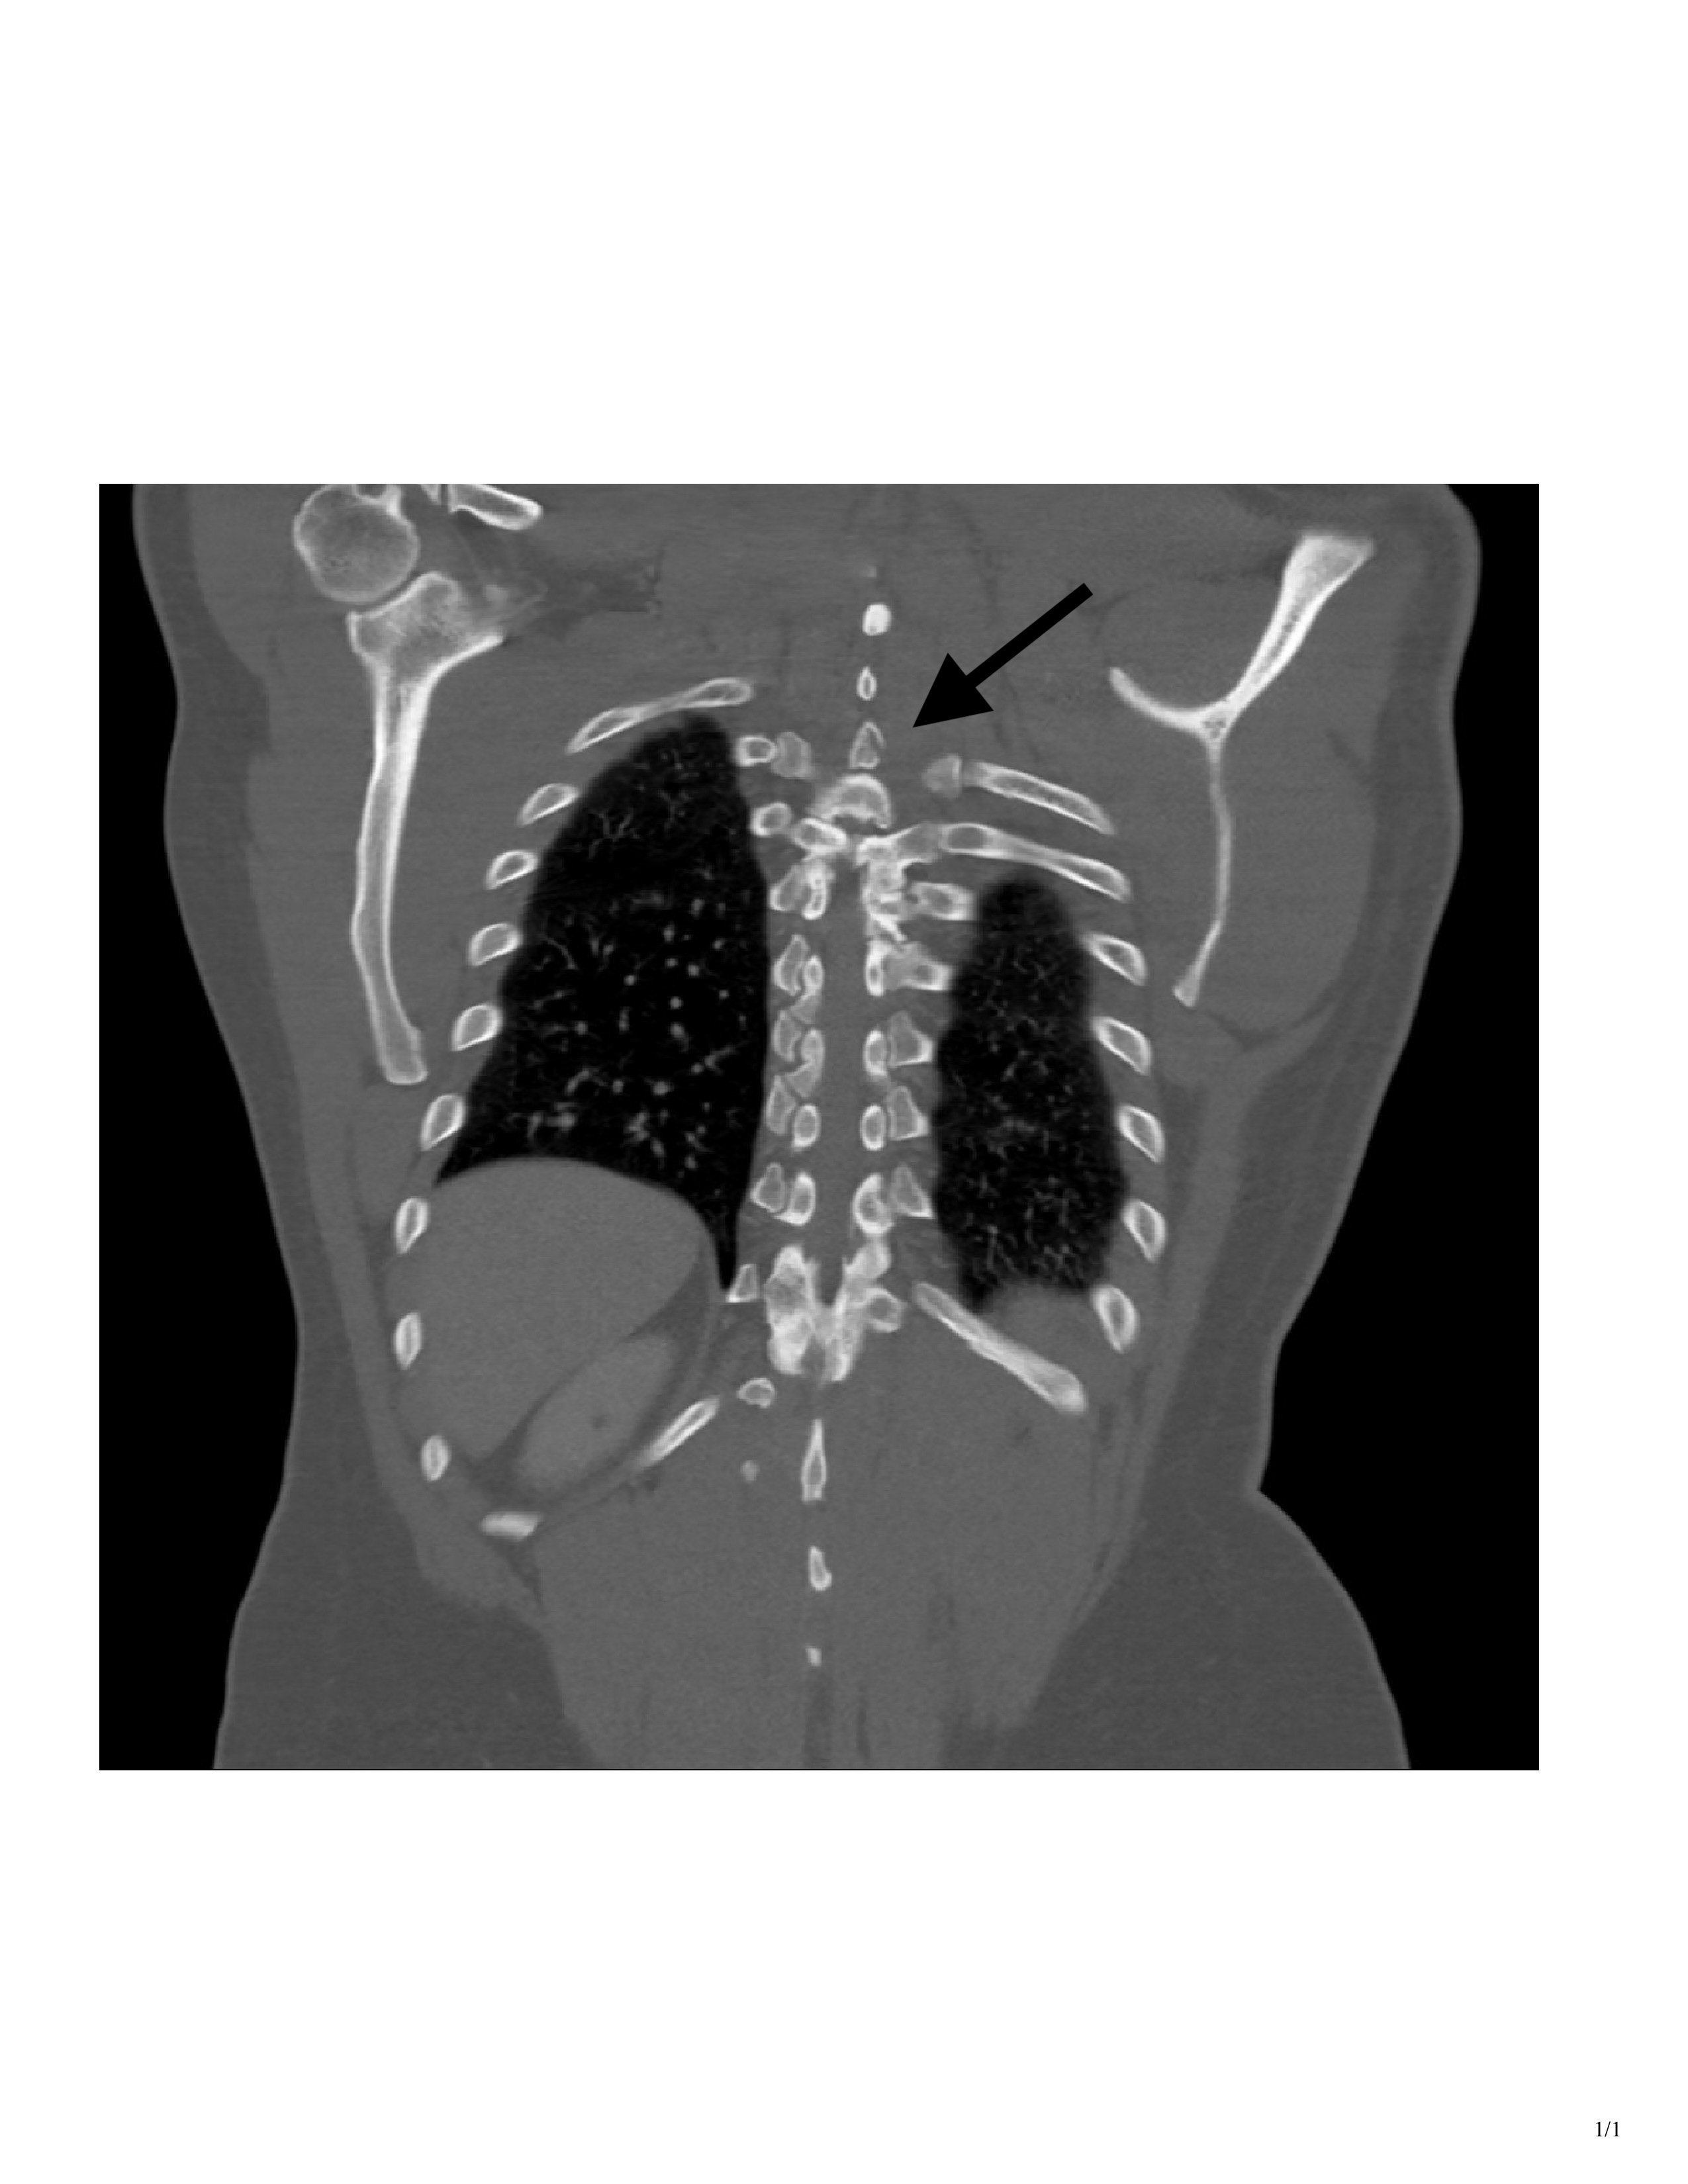

While opsoclonus-myoclonus-ataxis (dancing eye-dancing feet syndrome) may seem rare and complex, its early identification in the ED can be life‑altering. When faced with an unusual movement disorder a